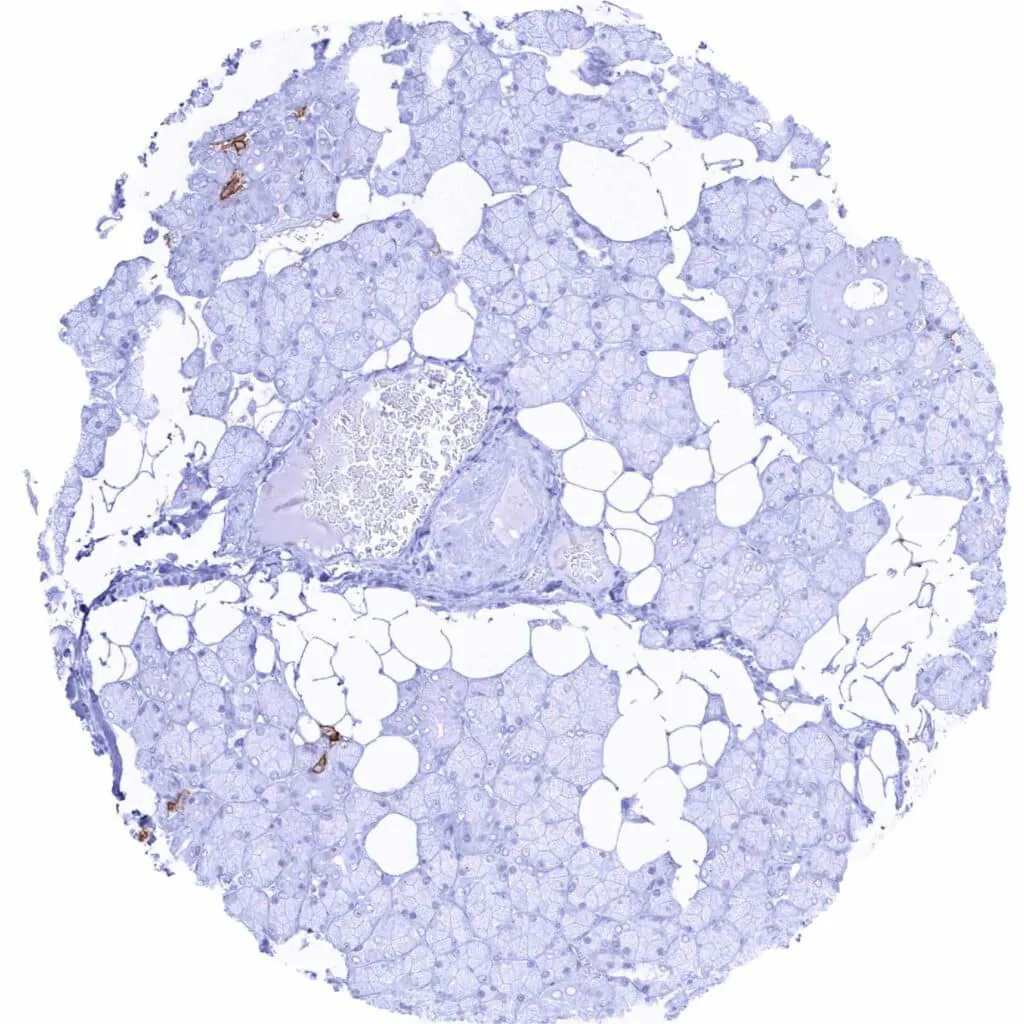

Testis